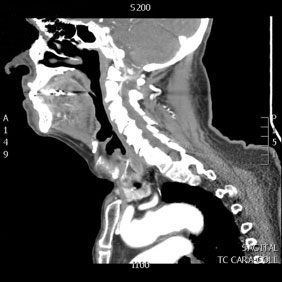

Tomografía computarizada Cuello

< Volver a "Tomografía Computarizada (TC) con Inteligencia artificial"Está indicado para el estudio de las diferentes patologías y estructuras del cuello (arterias, venas, ganglios, glándulas,…).

Normalmente para la correcta realización de este estudio es necesaria la inyección por vena de contraste yodado, que nos aportará una mejor caracterización y diferenciación de estructuras.